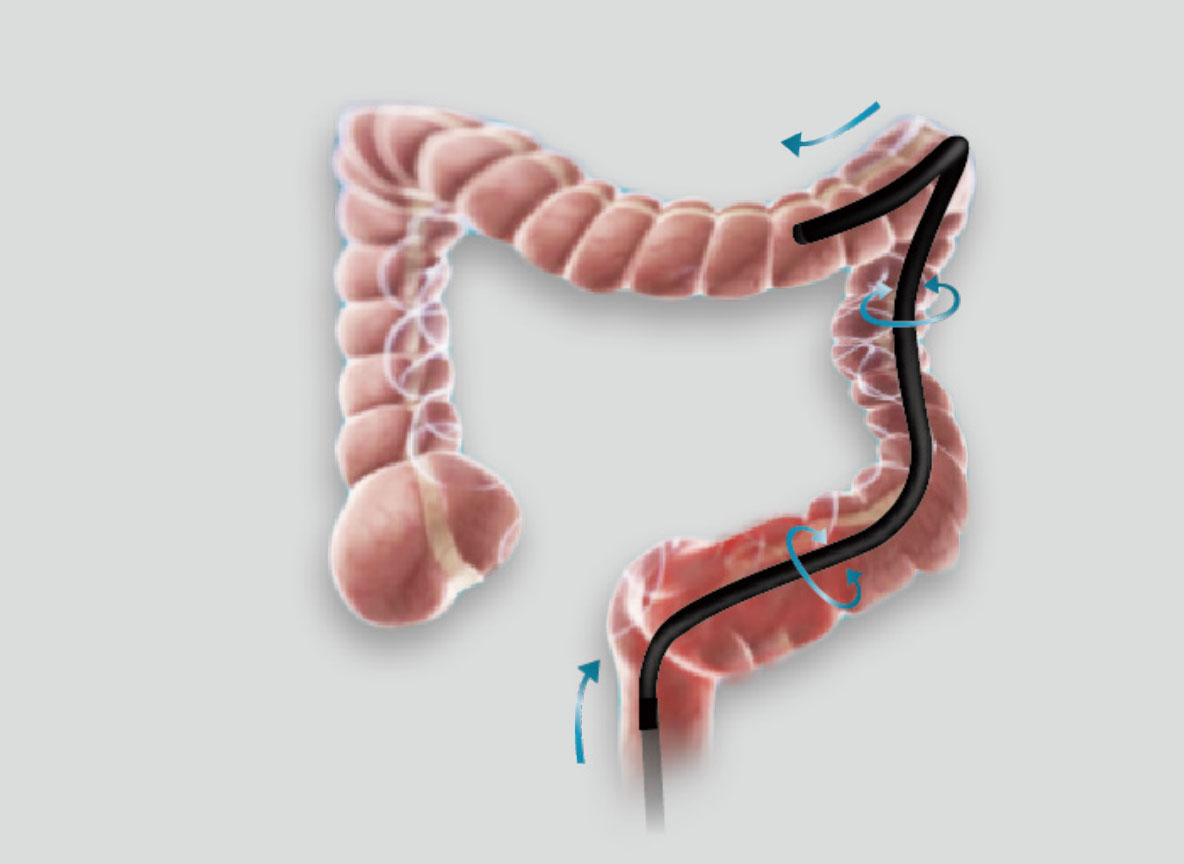

弯曲角度大,方便观察食管下段贲门、胃底部等难以观察到的部位,减少盲区。

带来镜体插入及诊疗新体验。